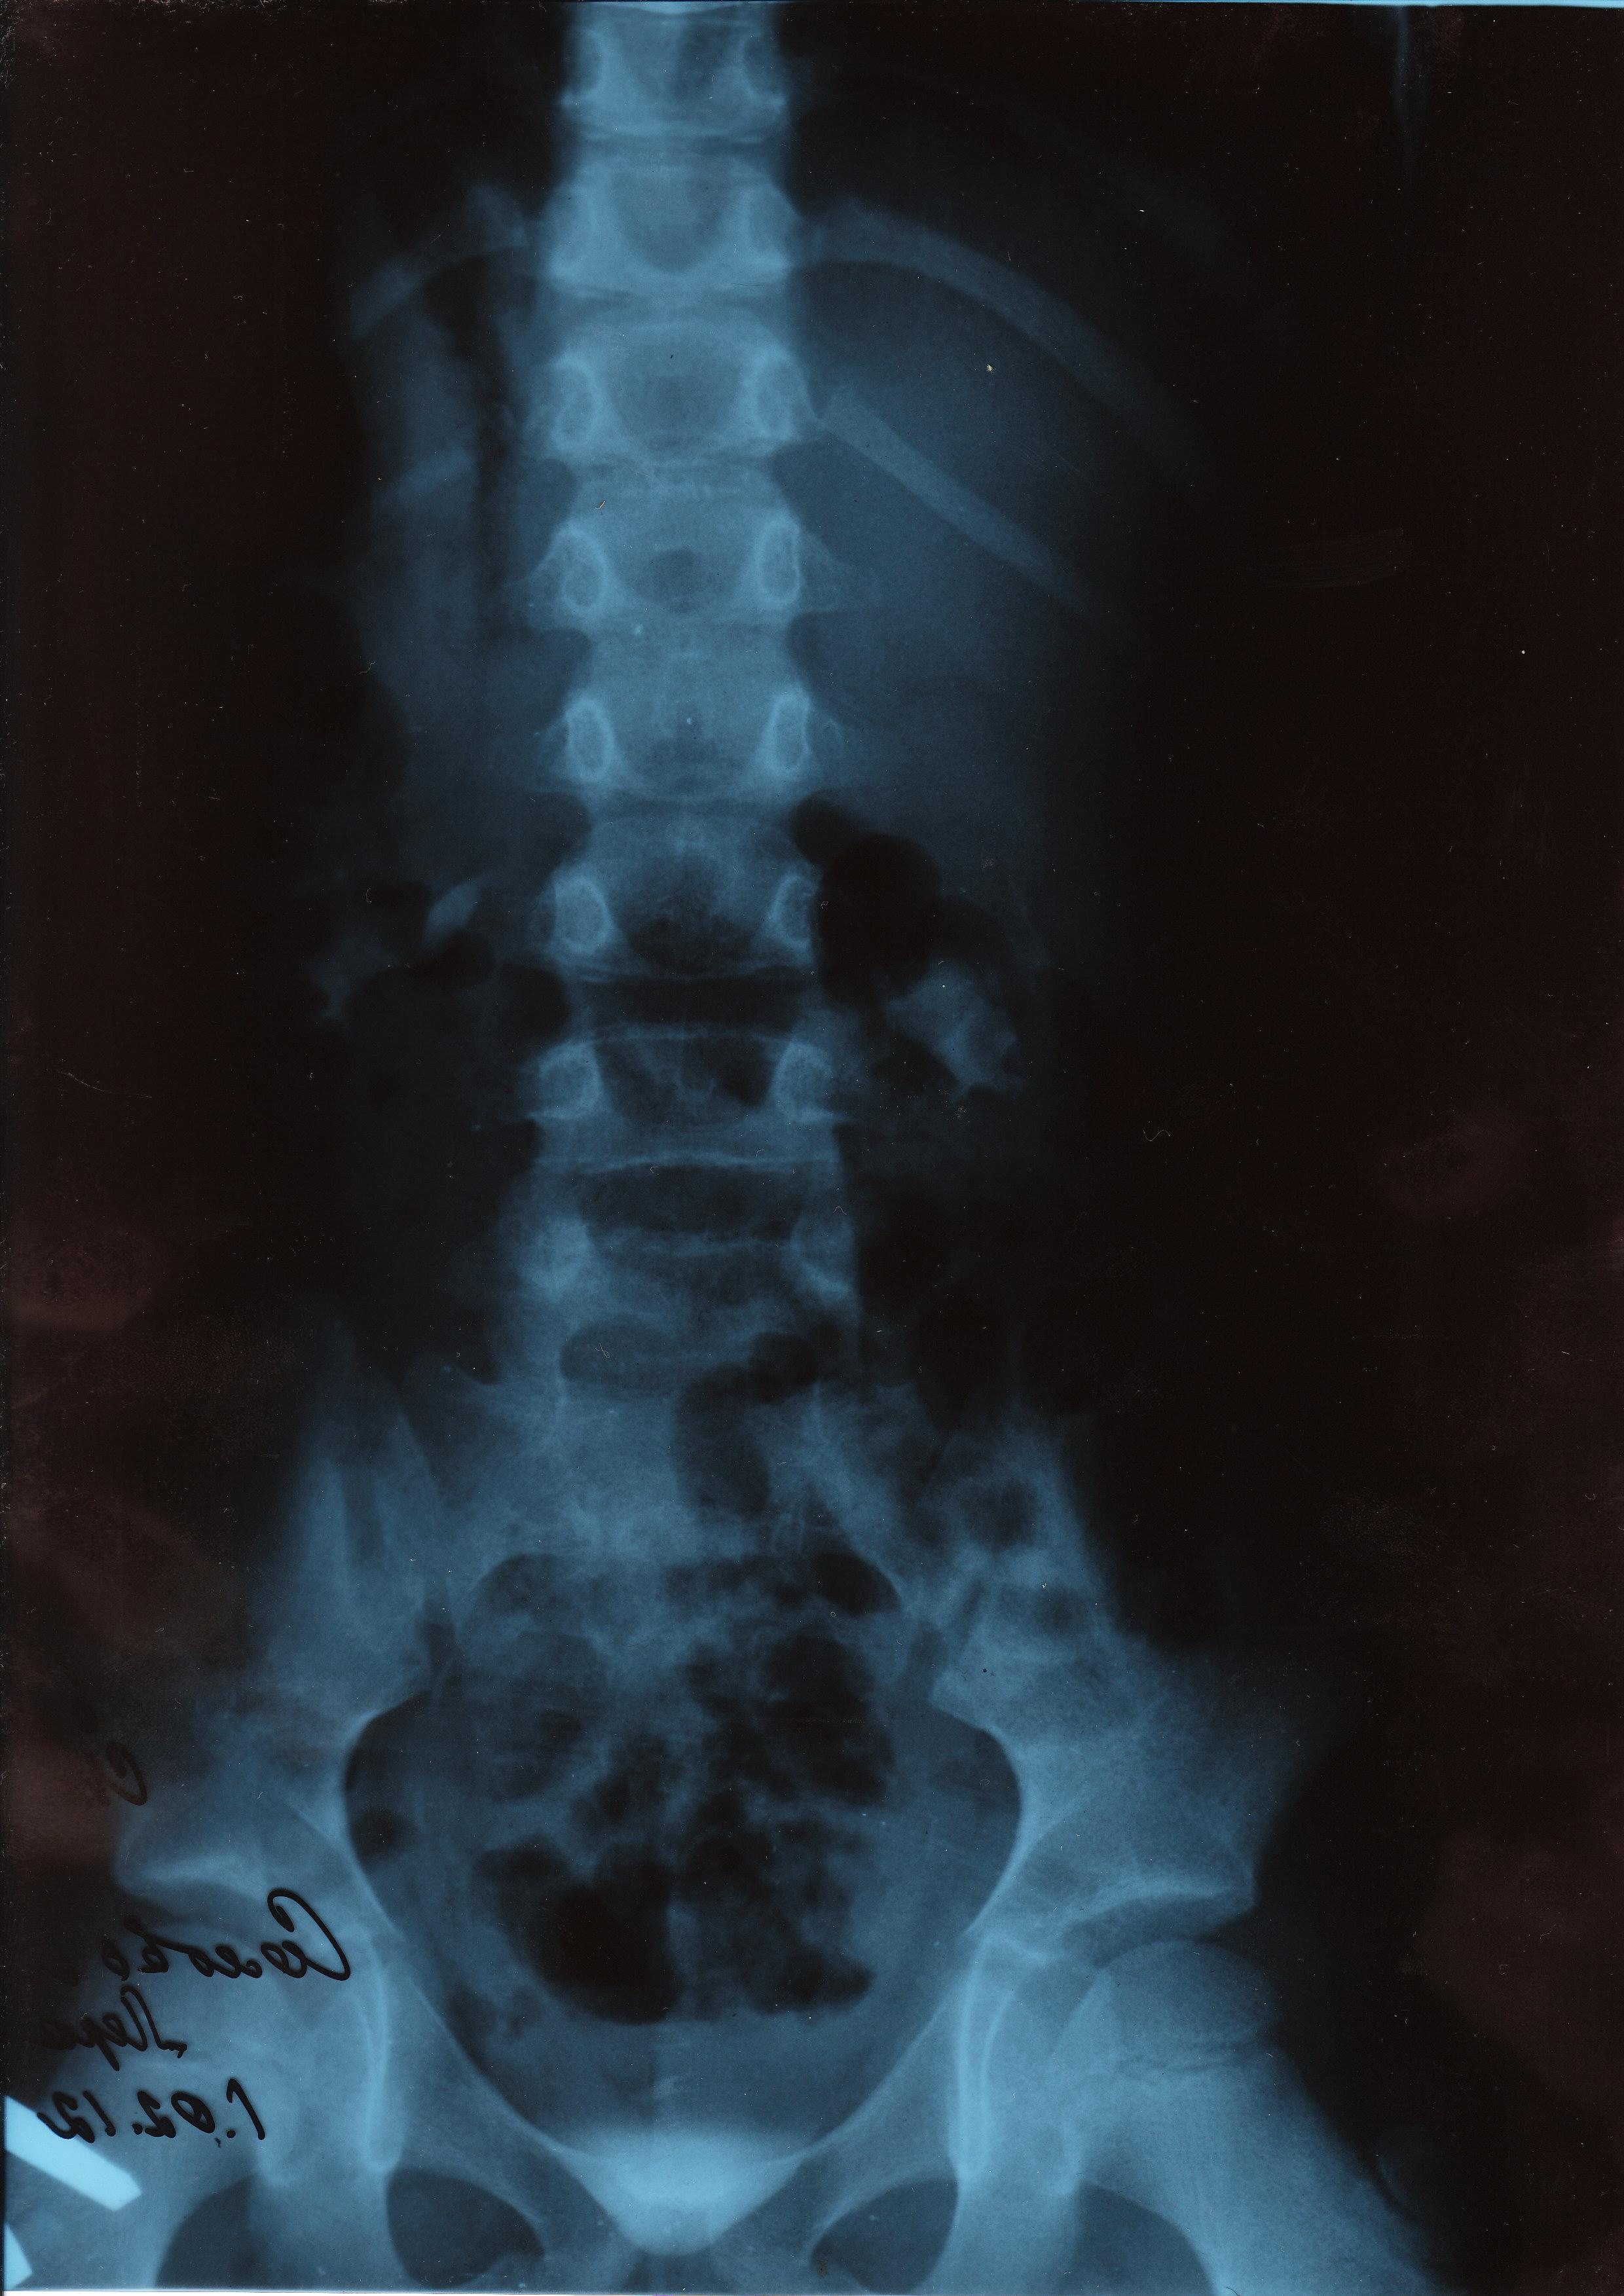

Для подробной оценки вашего состояния нужно увидеть снимки экскреторной урографии, данные статической нефросцинтиграфии. Присылайте на почту - тогда можно более точно ответить на ваш вопрос.